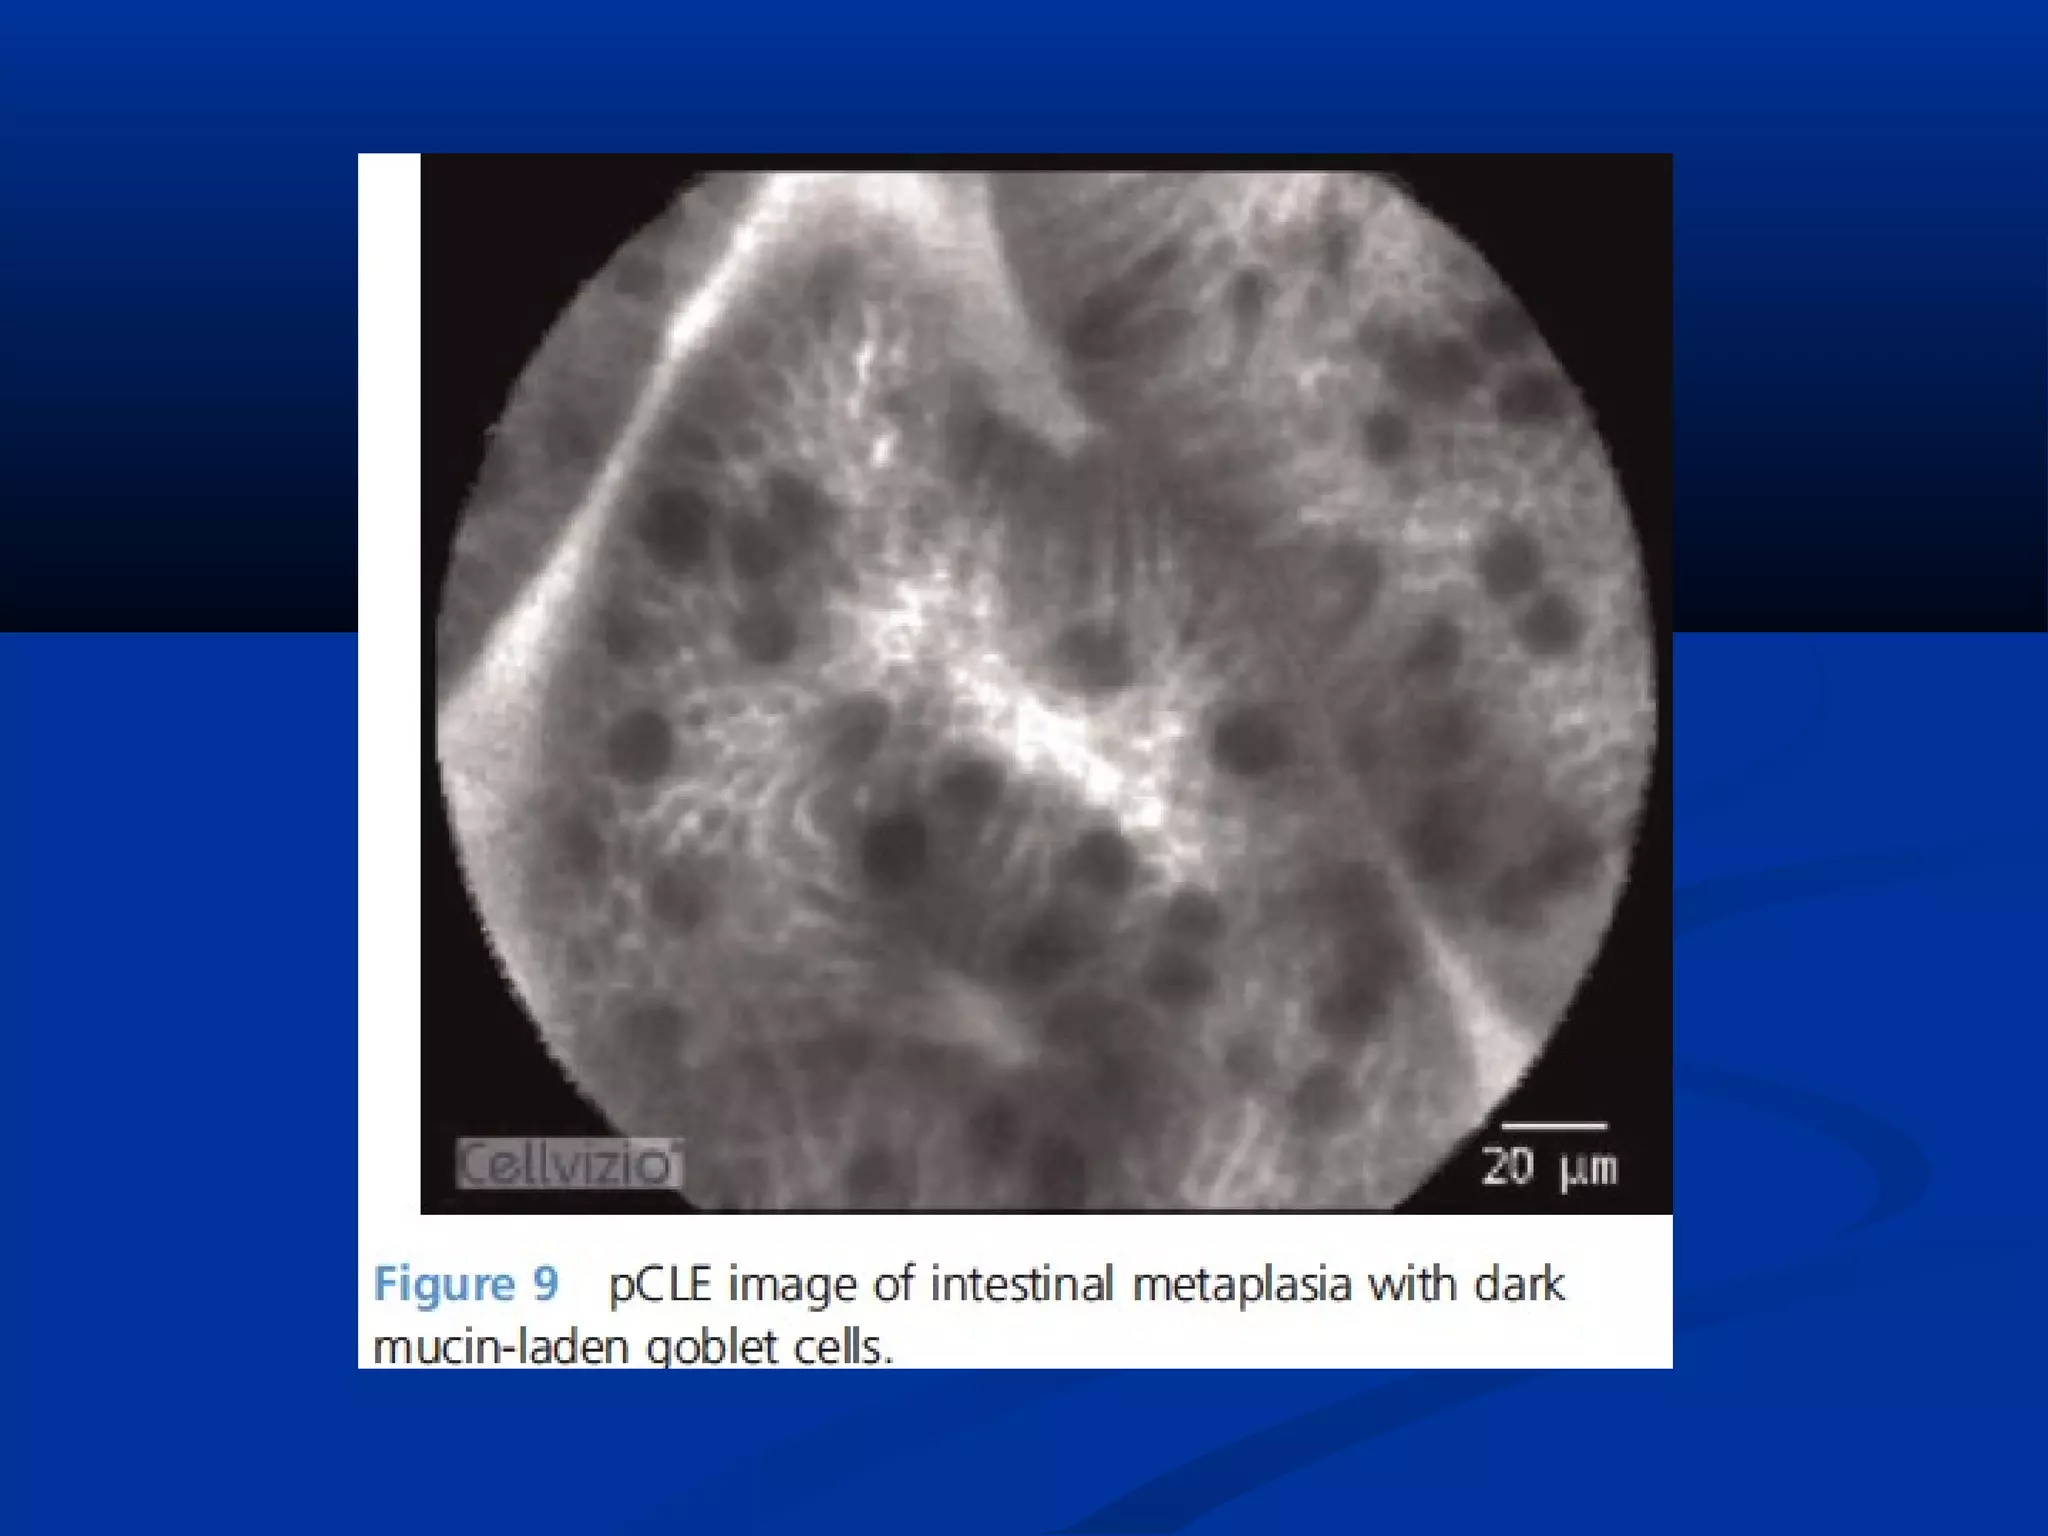

Types: CLETypes: CLE

 Confocal laser endomicroscopy works by focusing blue laser lightConfocal laser endomicroscopy works by focusing blue laser light

through a single lens onto a specific target.through a single lens onto a specific target.

 The reflected light is filtered through a pinhole, thereby reducingThe reflected light is filtered through a pinhole, thereby reducing

light scatter, creating highly detailed images from a thin focallight scatter, creating highly detailed images from a thin focal

plane.plane.

 This is available as a miniature scanner integrated onto theThis is available as a miniature scanner integrated onto the

endoscope tip or separately as a probe-based accessory fedendoscope tip or separately as a probe-based accessory fed

through the working channel of a standard endoscope.through the working channel of a standard endoscope.

 Administration of an intravenous fluorescent contrast agent isAdministration of an intravenous fluorescent contrast agent is

necessary in order to achieve delineation of the subsurfacenecessary in order to achieve delineation of the subsurface

architecture.architecture.

 CLE offers image detail comparable to histopathological sections.CLE offers image detail comparable to histopathological sections.

 A meta-analysis found the sensitivity of CLE in the detection ofA meta-analysis found the sensitivity of CLE in the detection of

neoplasia to be 89%, with fewer biopsies required compared withneoplasia to be 89%, with fewer biopsies required compared with

WLE assessment.WLE assessment.